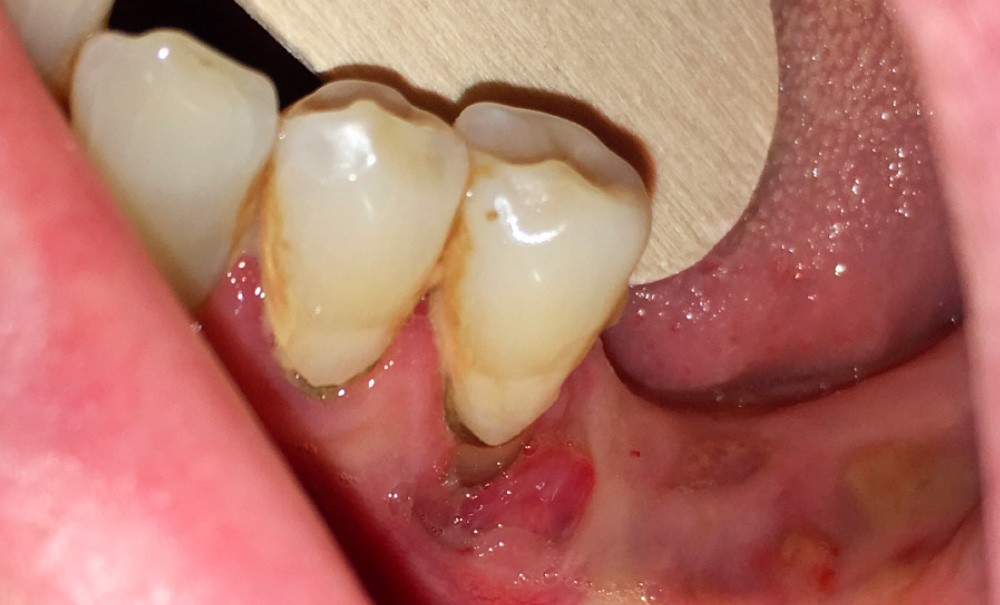

Pour les actes invasifs, une suspension de traitement pourra être discutée avec le médecin prescripteur, afin de réduire le risque infectieux au moment de l’acte, mais aussi en postopératoire [1, 2]. La thérapeutique sera reprise lorsque la cicatrisation sera complète. Il est évident que cette suspension de traitement ne doit pas altérer le pronostic de la pathologie et l’état général du patient. En cas d’urgence, les actes nécessaires doivent être entrepris sans délai (fig. 3).